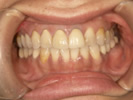

50代女性

![]() |

治療前 |

||

治療中。仮歯。 左上の奥にインプラント埋入。 噛みあわせ治療を行いました |

治療後 全体の歯で食事がおいしくできるようになったと喜んでおられました。 |